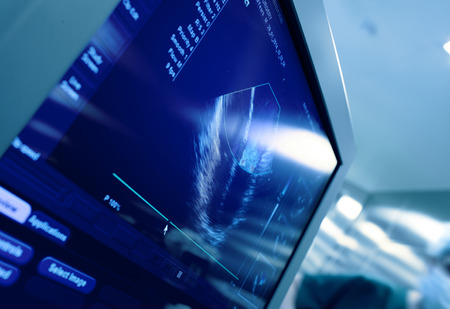

Heart on the screen of ultrasound machine